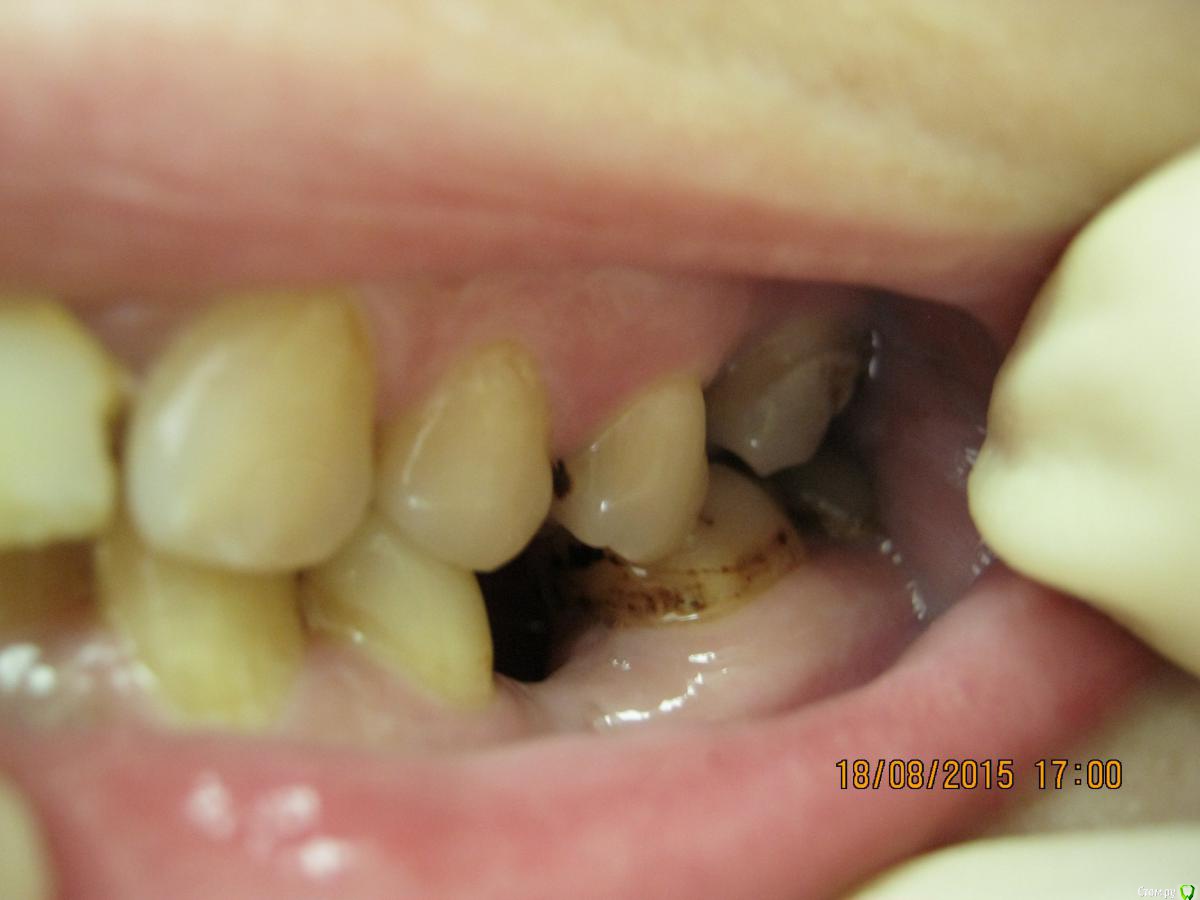

SeregaStomatolog Опубликовано 18 августа, 2015 Поделиться Опубликовано 18 августа, 2015 Добрый вечер уважаемые коллеги!В клинику обратилась пациентка с такой ситуацией во рту.Подскажите пожалуйста что можно сделать и с чего начать. Ссылка на комментарий

SeregaStomatolog Опубликовано 18 августа, 2015 Автор Поделиться Опубликовано 18 августа, 2015 Сделав как хочет пациентка вы не получите красивый результат, которого она ждет! и получится что вы не смогли реализовать ее мечты , а значит доктор неахти)) да и вы не особо результатом будете довольны, вам это надо? Если в эстетике проблем нет, восстановите функцию. Ненужное удалить, длинные зубы дэпульпировать, укоротить ну и коронуйте))Мне кажется если я возьмусь,то все равно не буду результатом доволен,т.к. все реализовать не получится.Самая большая проблема в области отсутствующих 1.6,1.7-зубо-альвеолярное удлинение 4.6,4.7 настолько велико,что они практически касаются слизистой в области 1.6,1.7. Ссылка на комментарий